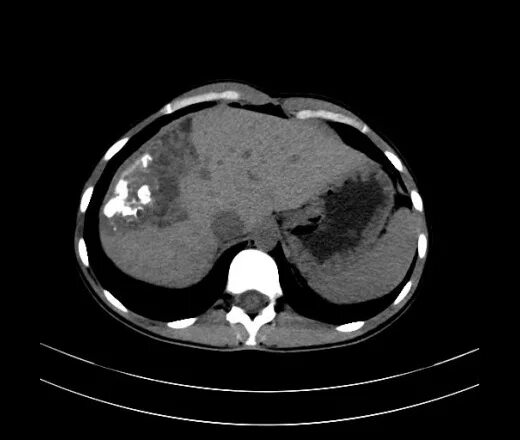

Образования печени кт